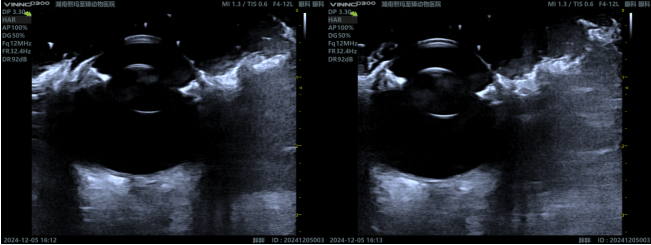

Ocular Ultrasound: